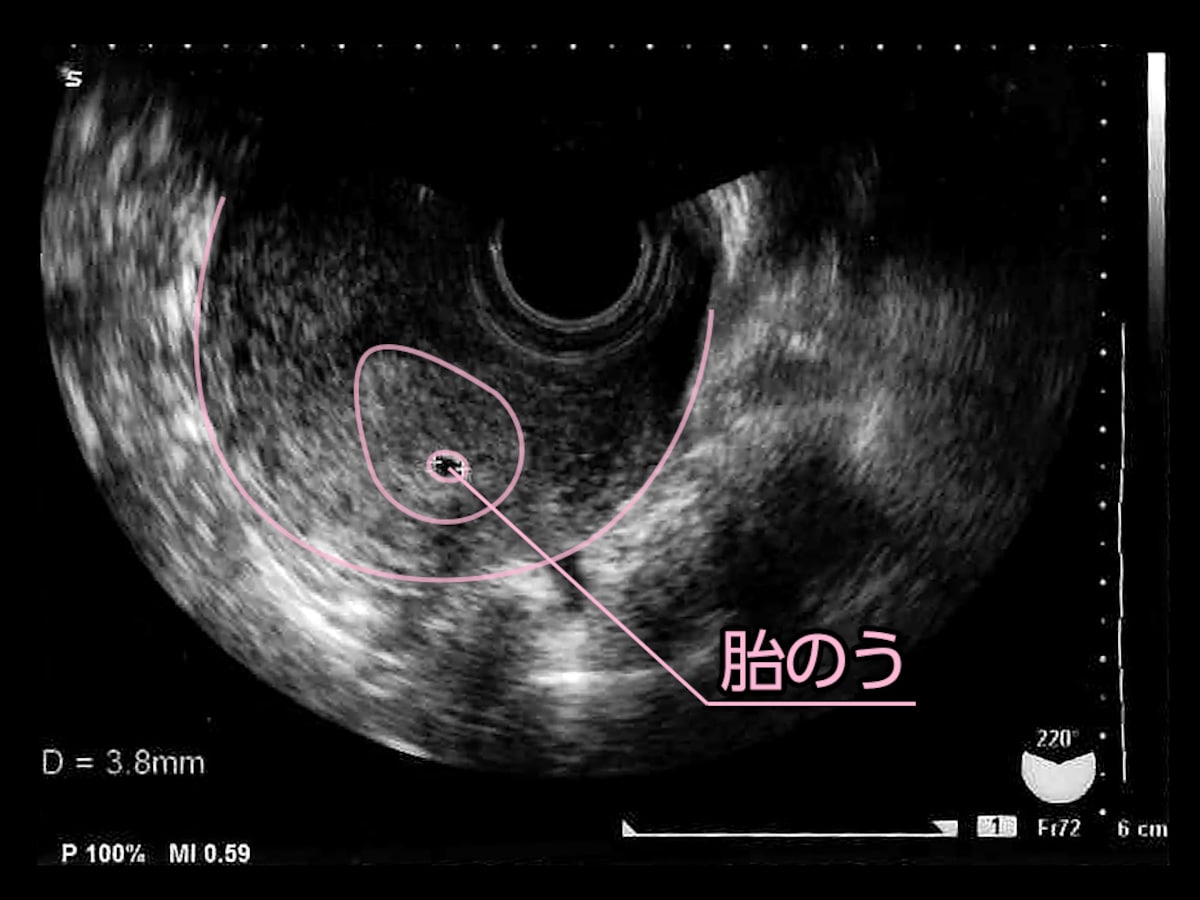

5周4日 胎嚢

妊娠5週4日 5w4d の超音波 エコー 写真

妊娠5週4日 5w4d の超音波 エコー 写真